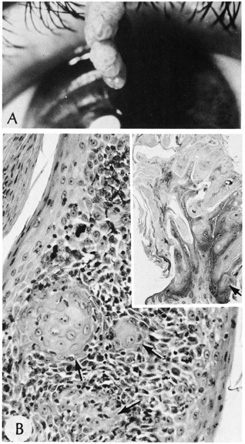

An external hordeolum (stye) (Fig. 4) results from an acute purulent inflammation of the superficial sweat and sebaceous glands or hair follicles of the eyelids, while an internal hordeolum occurs in the meibomian glands within the tarsal plates of the lids. They are characterized histologically by dense inflammation containing neutrophils and foreign body multinucleated giant cells around intact or ruptured appendegeal structures. A chalazion is chronic inflammation of a meibomian gland (deep type) or zeisian sebaceous gland (superficial type) resulting in a clinically firm, painless nodule of the eyelid (Fig. 5A). Histologically, there is deep dermal or subcutaneous suppurative granulomatous inflammation containing neutrophils, plasma cells, lymphocytes, histiocytes, and giant cells in a zonal configuration around central lipid material (see Fig. 5B).

Fig. 4. Hordeolum—Clinical photograph of tender erythematous mass on the upper eyelid. (Photo courtesy of William Morris, M.D.)

Fig. 5. Chalazion—A. Typical clinical appearance of chalazion. B. Lipogranulomatous reaction with epithelioid cells, lymphocytes, and plasma cells surrounding a central nidus of Meibomian gland secretion. Clear area in center represents lipid material dissolved out during processing of tissue. Giant cells are sometimes seen (hematoxylin and eosin stain). (Photos courtesy of William Morris, M.D.)